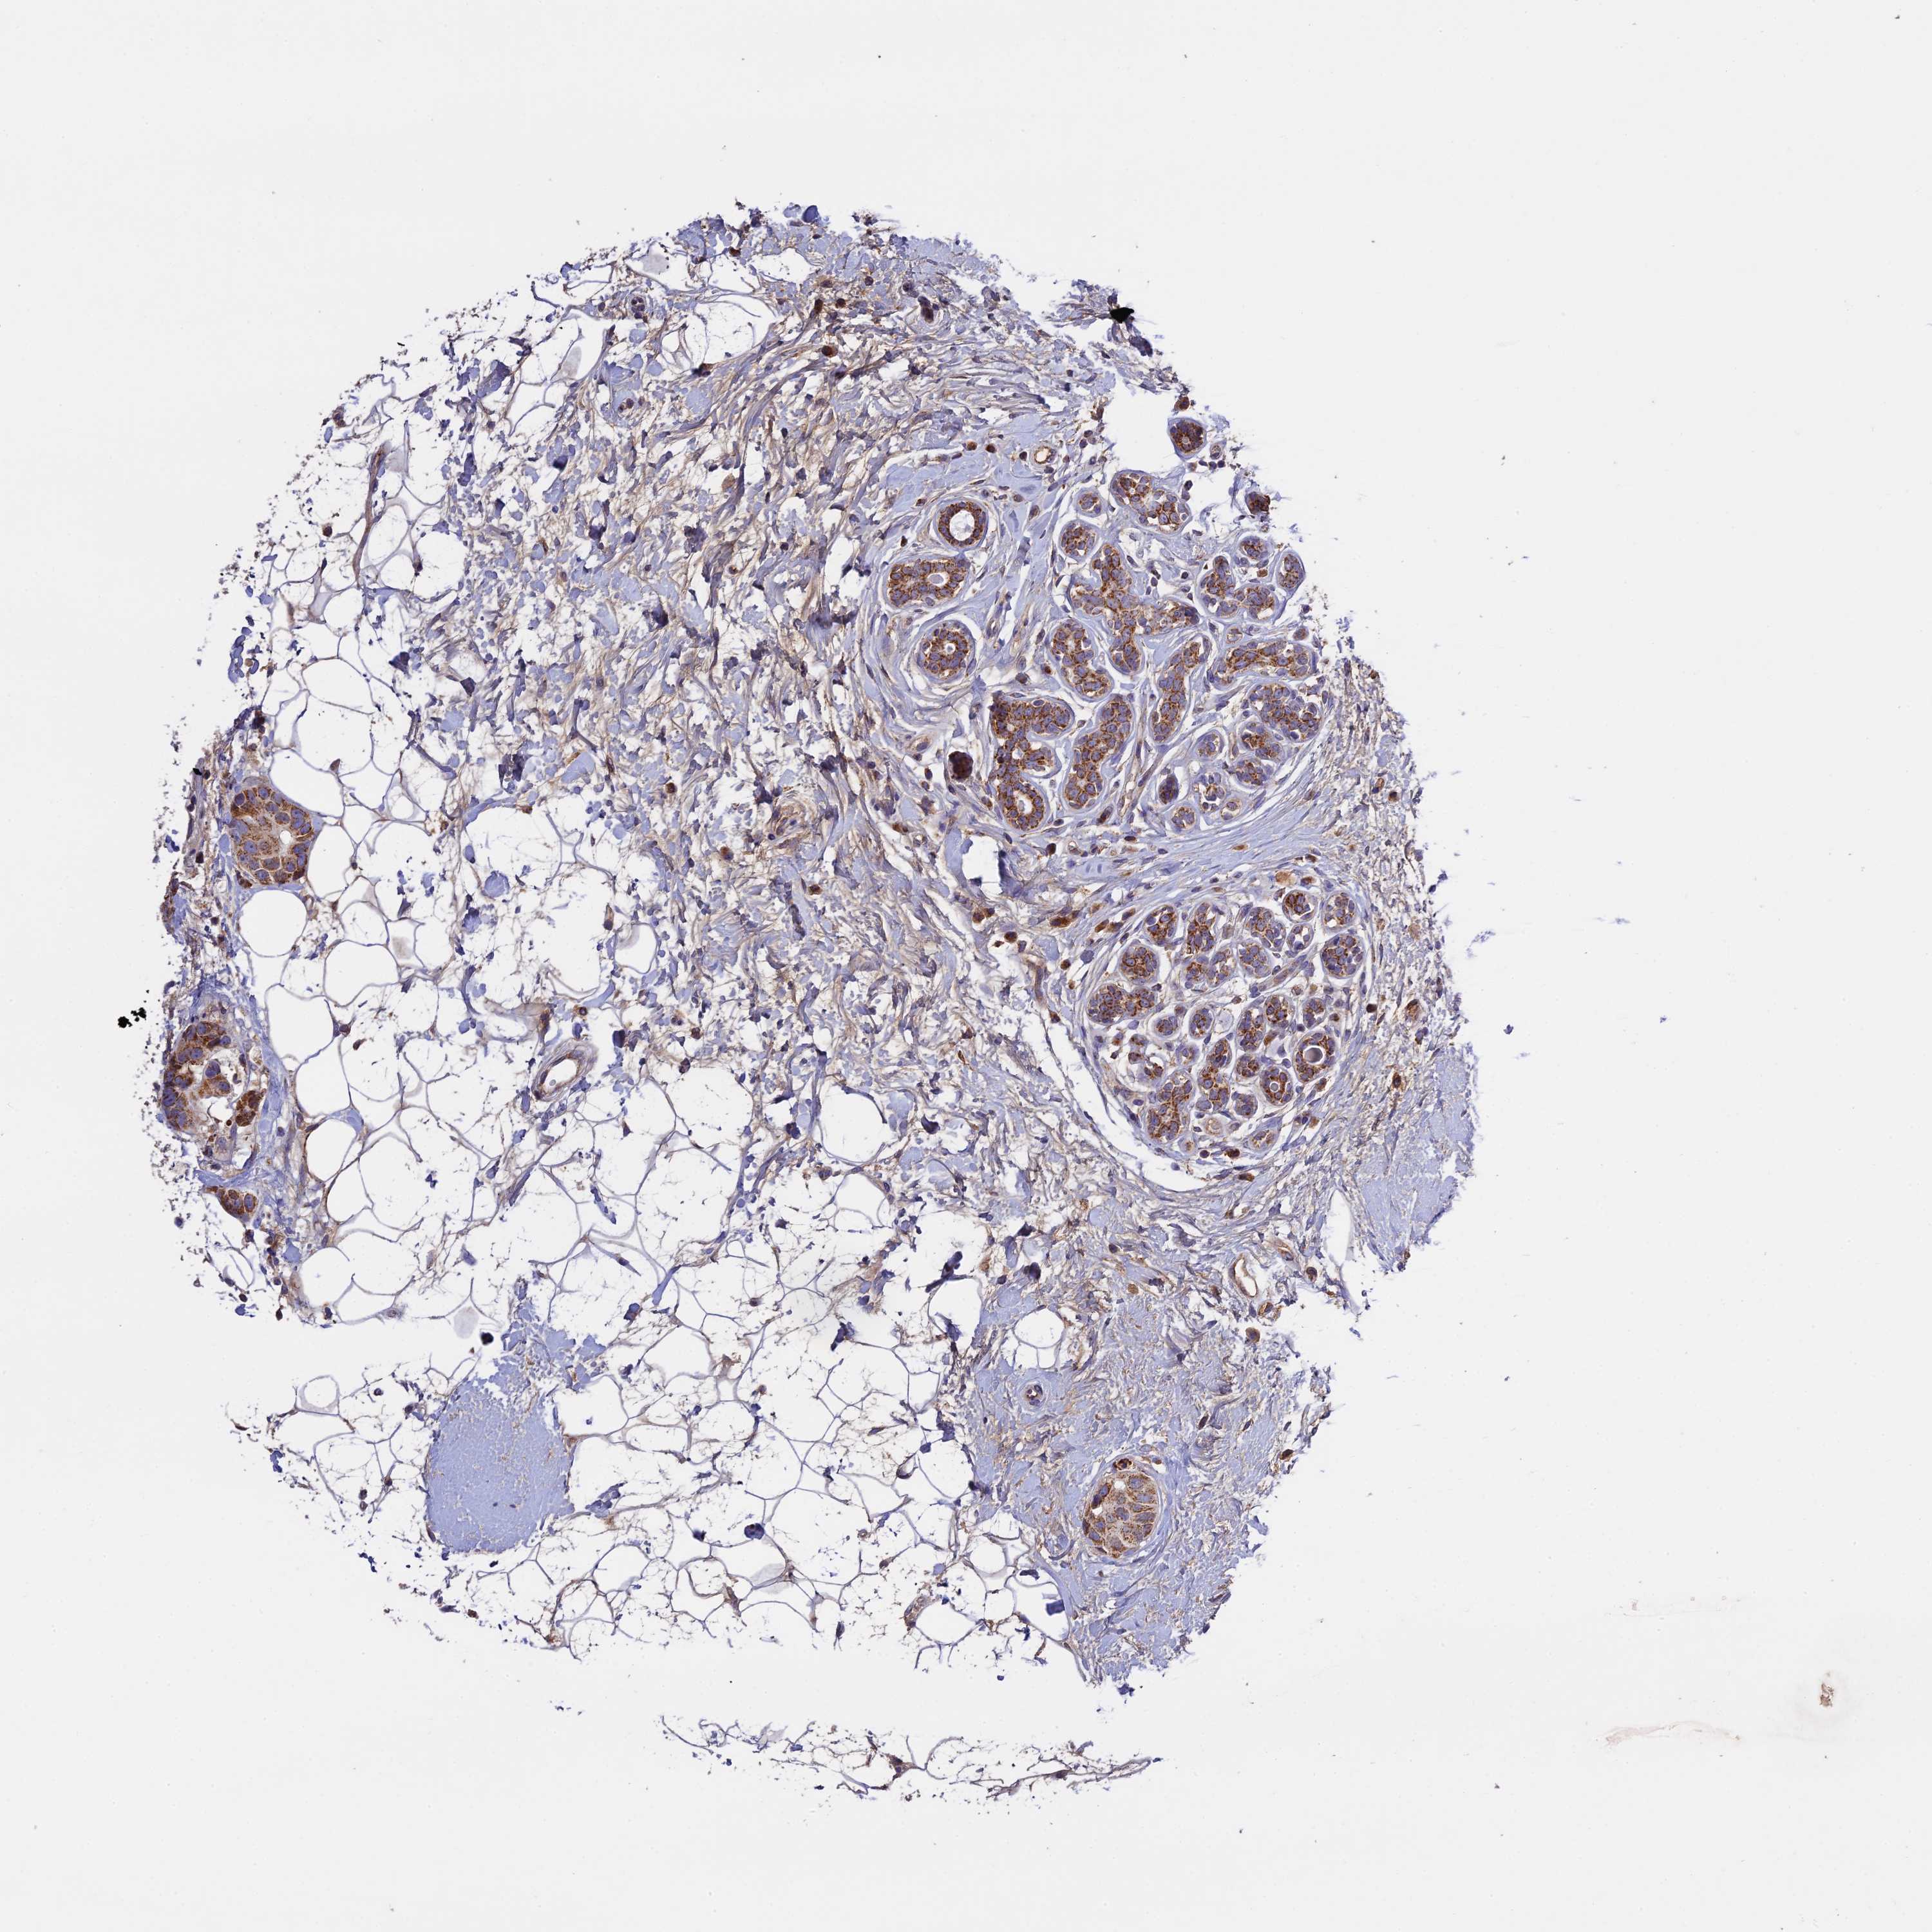

BRCA TCGA BRCA VALIDATION PROTEIN EXPRESSION

ANTIBODIES

AND

VALIDATION